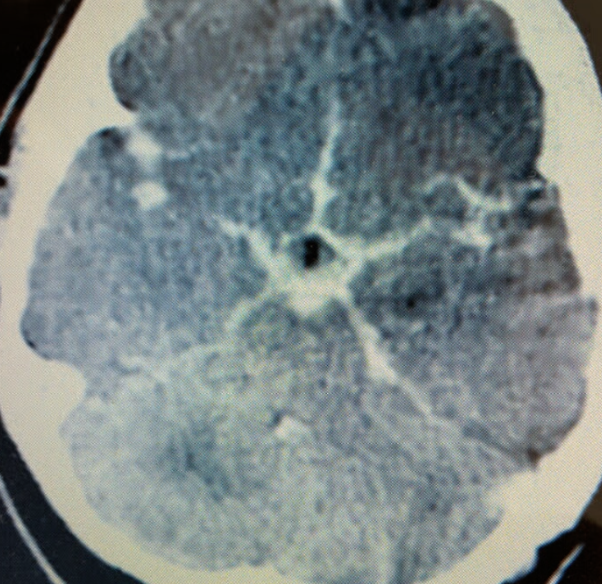

What’s ur finding ?

Star sign!!

Diagnosis?

Subarachnoid hemorrhage